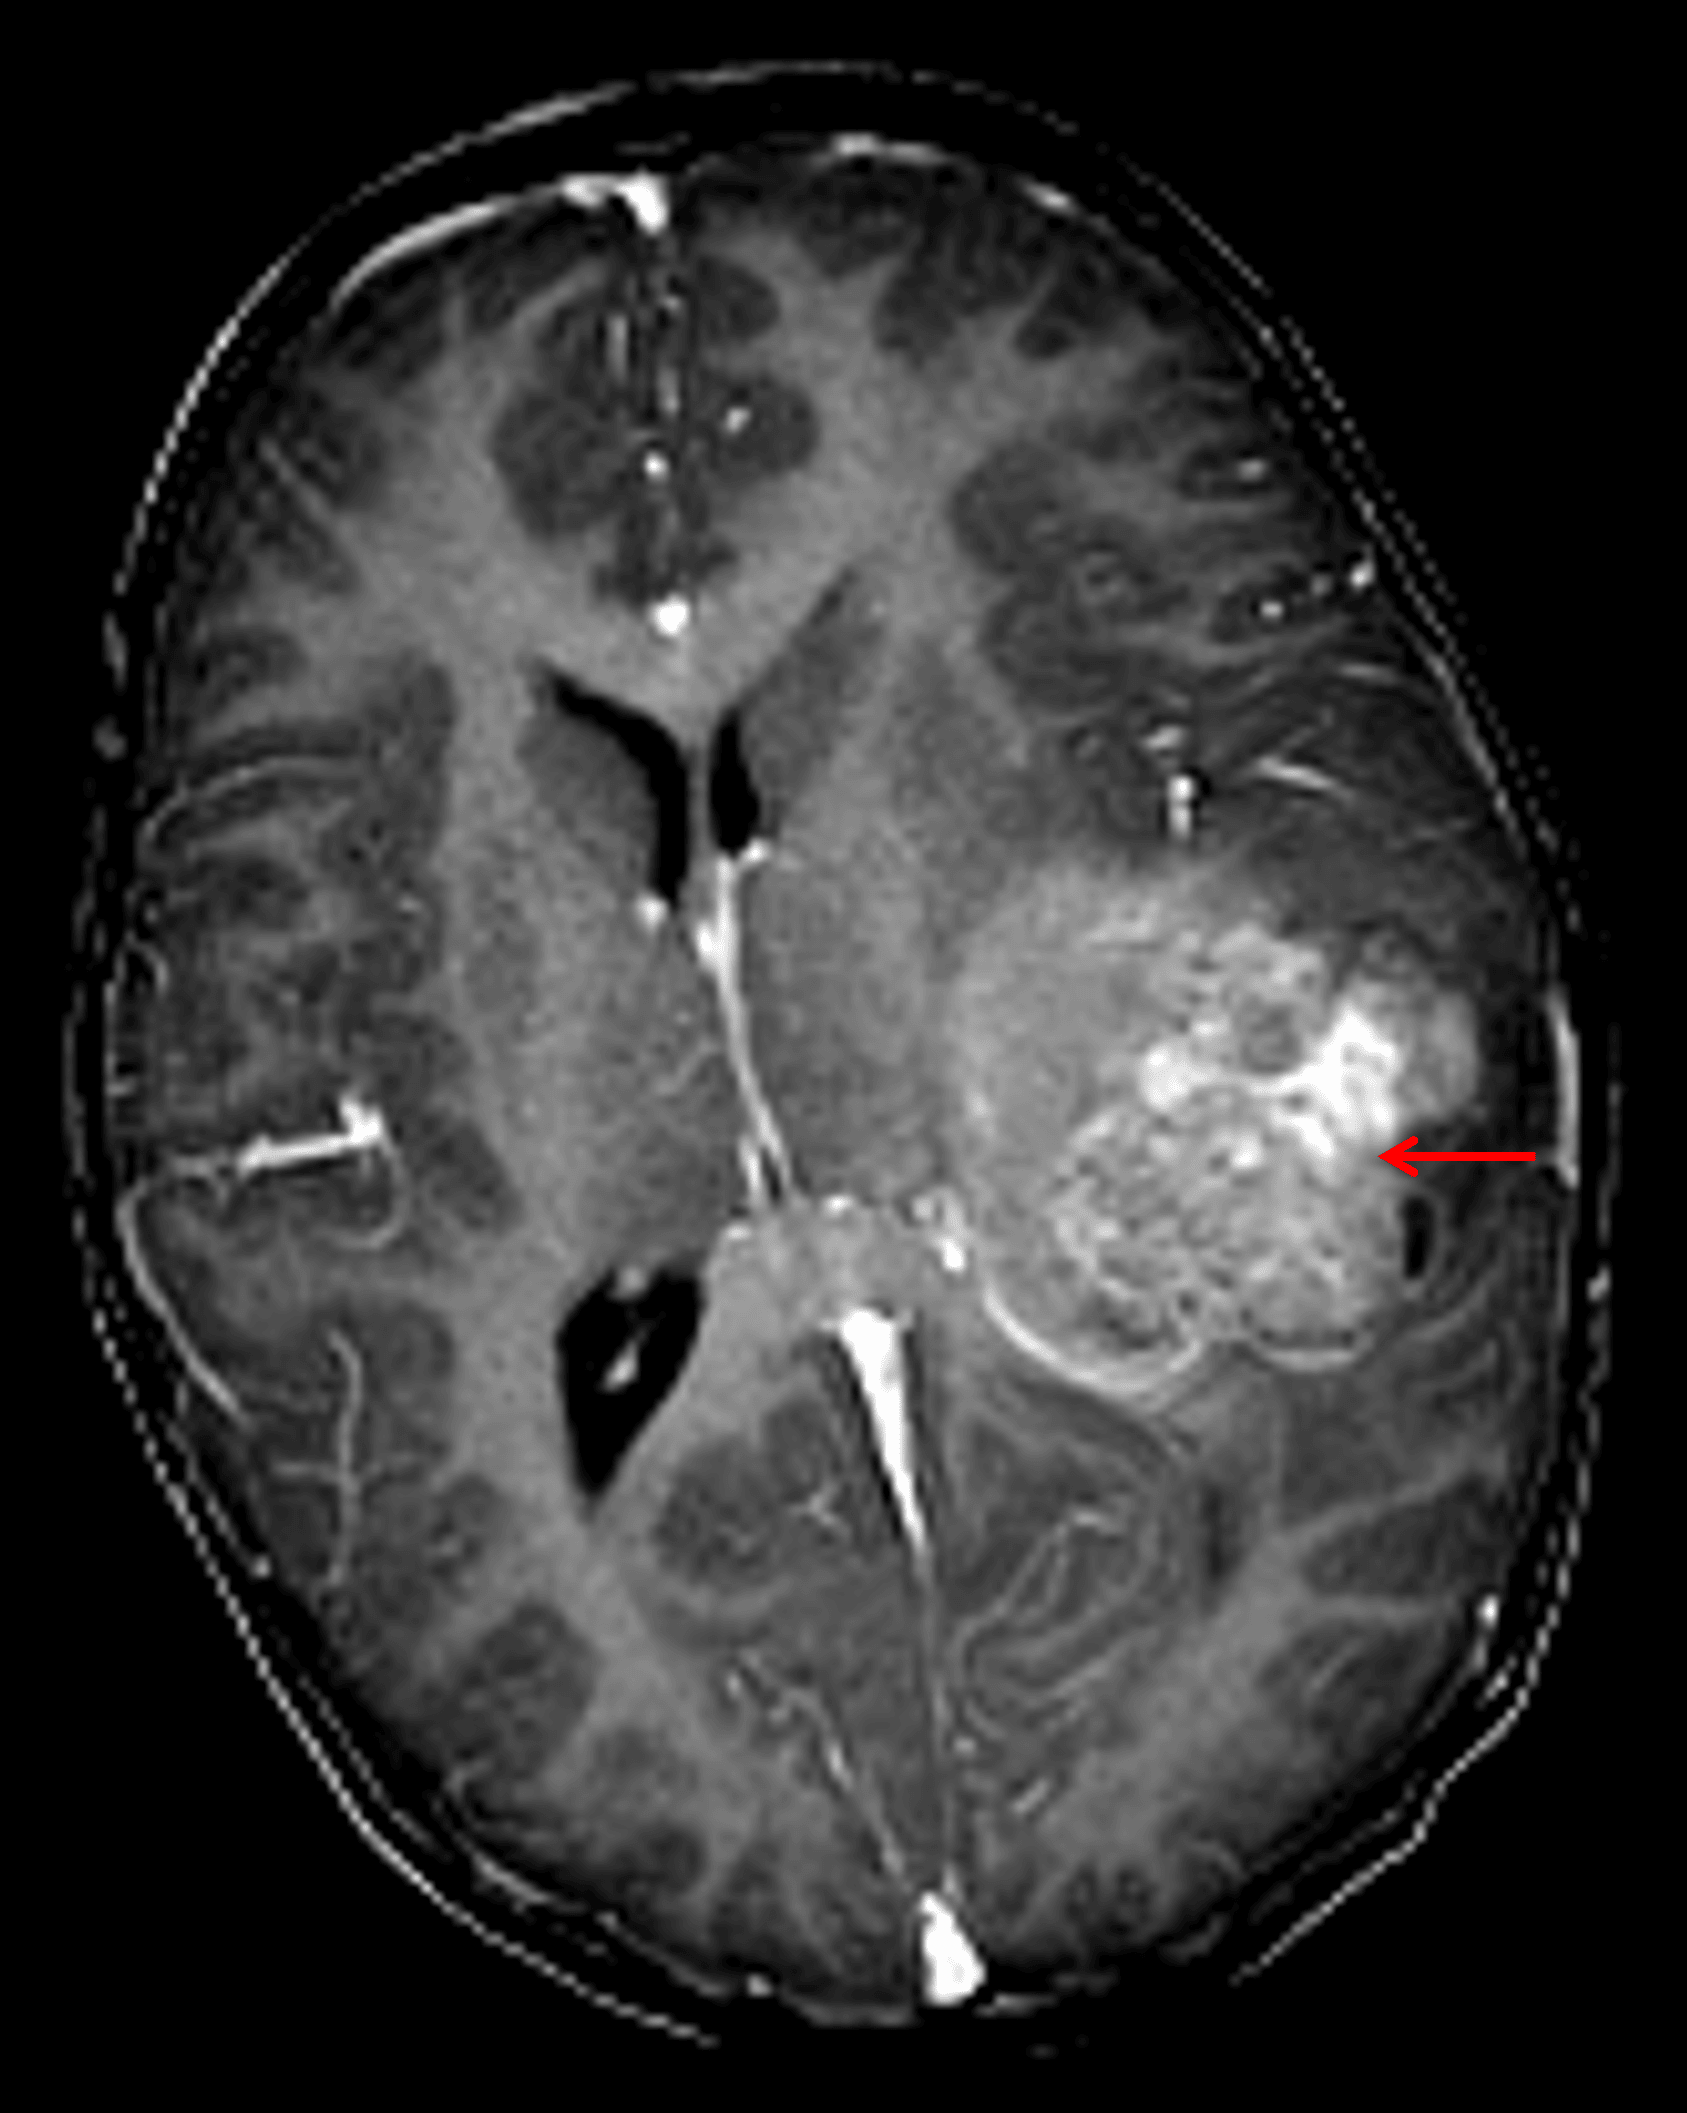

- Heterogeneous mass in the left cerebral hemisphere measuring 5.3 x 5 x 6 cm

- Corresponding heterogeneous enhancement with matching areas of restricted diffusion

- Surrounding vasogenic edema and associated mass effect resulting in local sulcal effacement, crowding of the left lateral ventricle, and 10 mm left-to-right midline shift

Heterogeneously enhancing mass in the left cerebral hemisphere (red arrow) with associated local mass effect and midline shift.